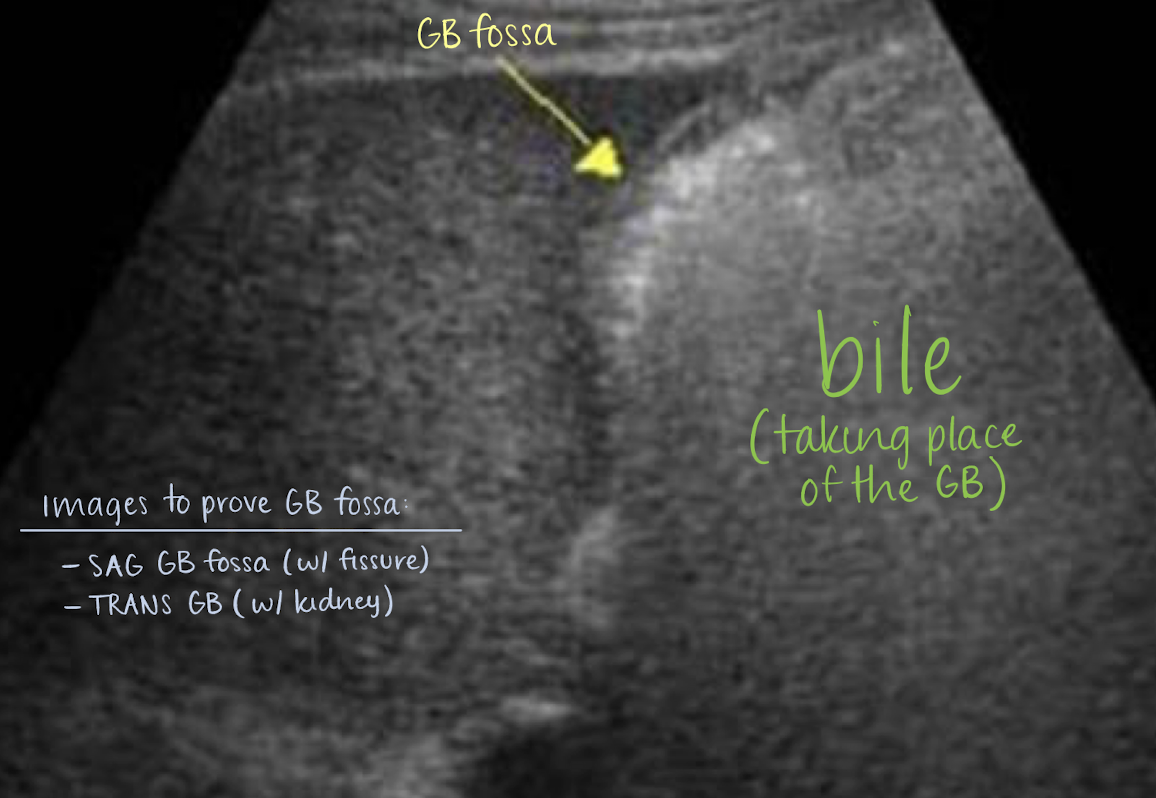

cholecystectomy

removal of GB —>

sphincter of Oddi loses tonus

bile flows freely into duodenum (biloma)

extrahepatic bile ducts dilate, up to 1 cm

what are some post complications of cholecystectomy?

biloma

stones

abscess

??